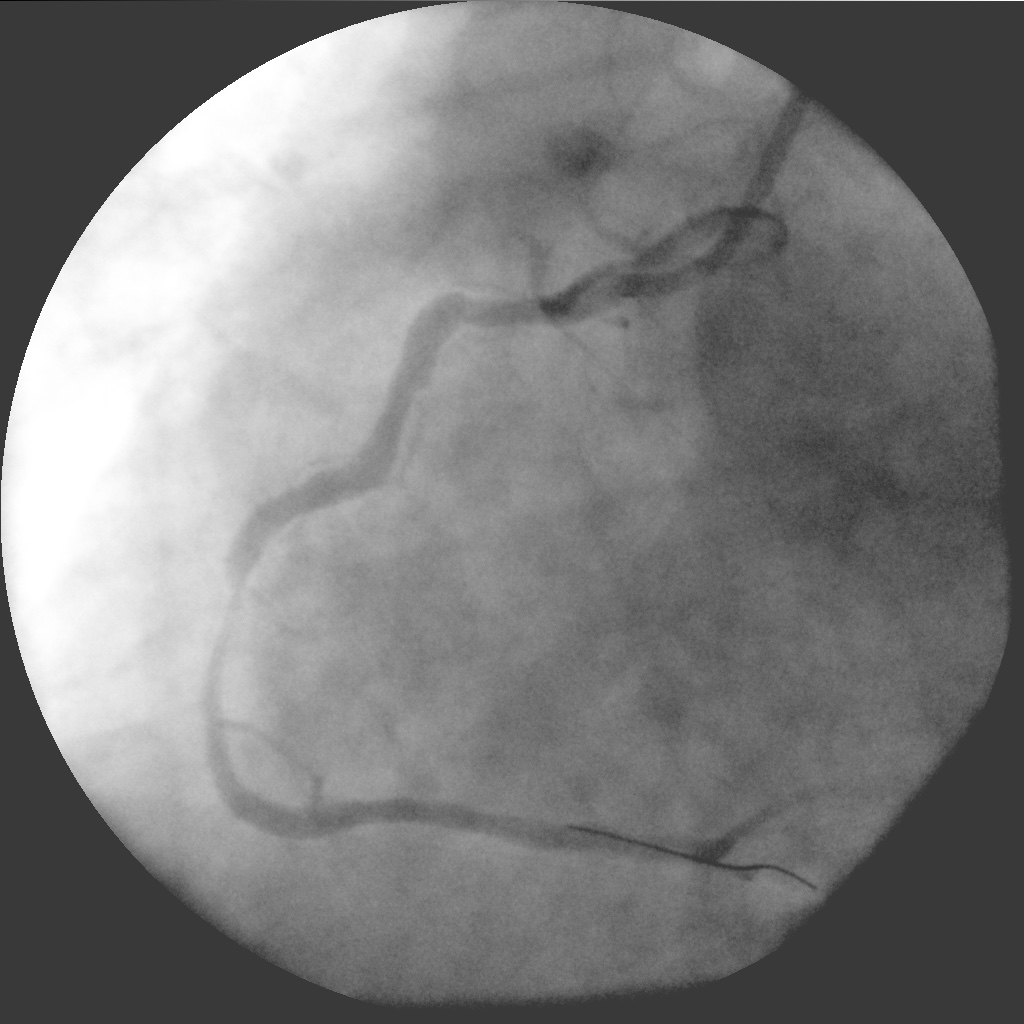

Позиционирование и стент в стент. Готово!

IM-0001-0021.jpg

IM-0001-0021.jpg [ 262.08 KiB | Просмотров: 51856 ]

IM-0001-0058.jpg

IM-0001-0058.jpg [ 227.83 KiB | Просмотров: 51856 ]